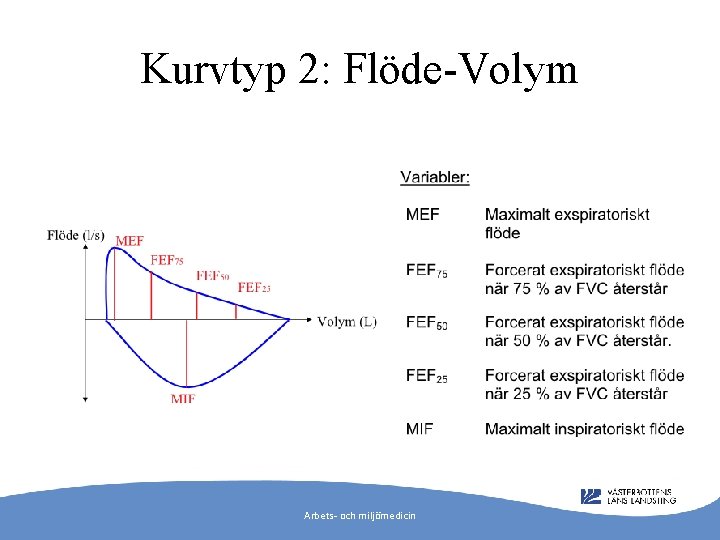

Kurvtyp 2: Flöde-Volym Arbets- och miljömedicin

Vad behövs för tolkning? • • VC (vitalkapacitet) FVC (forcerad vitalkapacitet) FEV 1 (forcerad ensekundsvolym) FEV% (FEV 1/VC eller FVC) Arbets- och miljömedicin